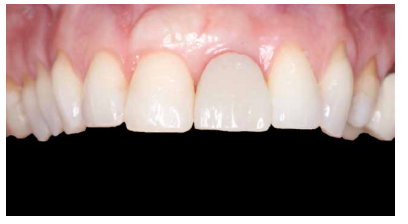

Se llevó a cabo una primera revisión del procedimiento quirúrgico a los 7 días. Se observó una correcta cicatrización inicial de los tejidos blandos y ausencia de patología infecciosa o inflamatoria (Figura 18). A los 14 días se realizó una segunda revisión en la que se retiró la sutura (Figura 19). La revisión al mes de la cirugía mostró una correcta estabilidad inicial de los tejidos blandos y duros, así como la ausencia de signos relacionados con el fracaso del procedimiento (Figura 20).

A los 4 meses se evidenció una correcta estabilidad del IOI fruto de un correcto proceso de osteointegración. Respecto a los tejidos blandos, se podía observar una disminución del volumen de la papila interdental (Figura 21). Dada la ausencia de signos y síntomas y la correcta osteointegración del IOI, se realizó la modificación del perfil subcrítico con el fin mejorar la disposición del tejido blando gingival y favorecer la recuperación de dicha papila (Figuras 22 y 23).

A los 6 meses se puede observar una correcta disposición de los tejidos blandos, así como la estabilidad de estos en el tiempo debido al manejo de los mismos a través de la prótesis provisional (Figura 24). Se realizó además un control radiológico para conocer el estado de los tejidos duros (Figura 25).

Dada la correcta evolución del caso a los 6 meses, se llevó a cabo el registro de la posición del IOI y del perfil de emergencia mediante un transfer individualizado con el fin de replicar de forma fiel y detallada la arquitectura gingival (Figuras 26 y 27). Finalmente se colocó la prótesis fija final atornillada al IOI a los 7 meses del inicio del tratamiento (Figuras 28 y 29).